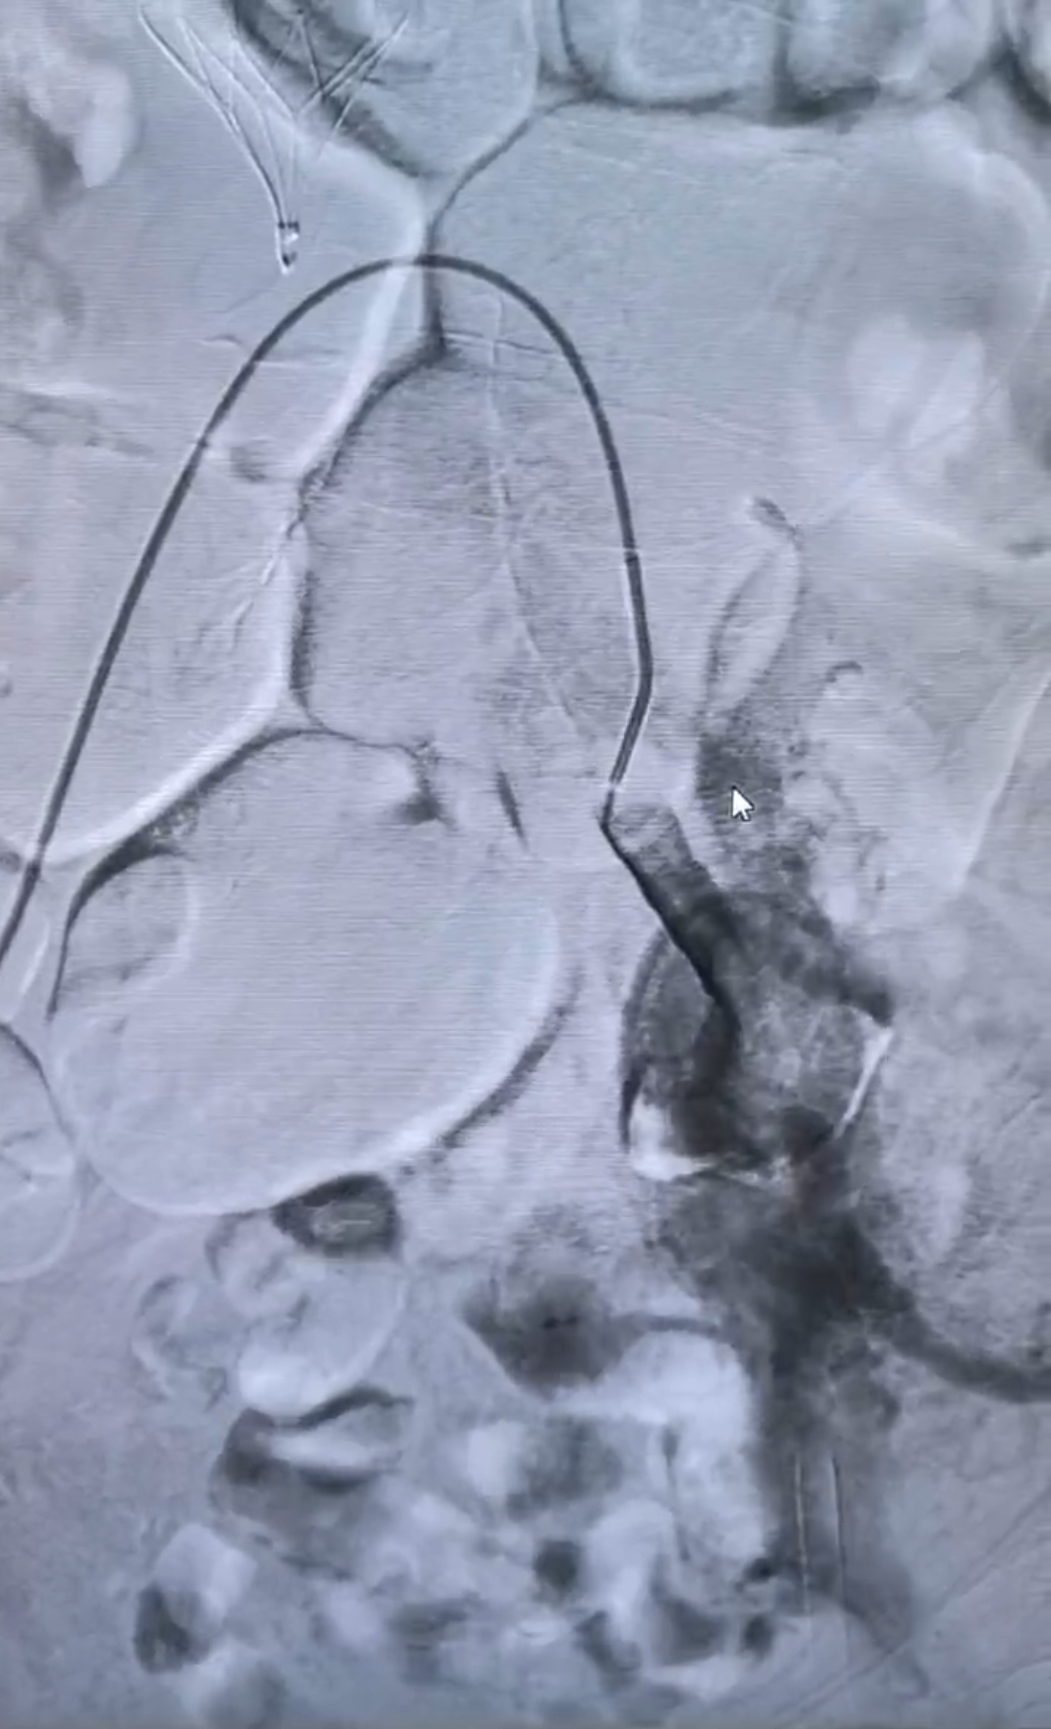

近期,一位89岁高龄患者因左腿严重肿胀、青紫来院,诊断为罕见的髂静脉闭塞合并下肢动静脉瘘。我院血管外科与介入科对其实施综合术后,患者腿部症状得到极大改善。

我院血管外科与介入科专家会诊后考虑患者出现股青肿表现,立即安排急诊手术。术中发现左髂静脉闭塞,股静脉逆向快速血流;左侧髂内动脉、左股动脉弥漫性动静脉瘘,前者为主,经左髂静脉回流。手术团队帮助患者开通闭塞的静脉并时刻保持血流通畅。术后第一天患者腿部就明显消肿,术后第二天腿部情况已与对侧基本一致。患者家属感叹,两年的老毛病,竟然一夜就消了。